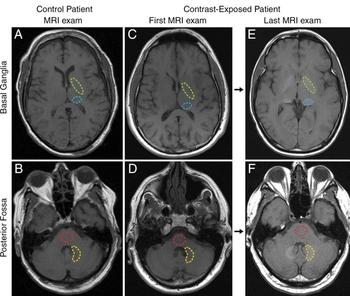

Imaging with gadolinium does not put patients at risk for adverse neurologic outcomes later in life.